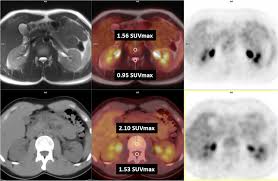

The F-Conal FDG PET scan uses a radiotracer called F-18 Fluorodeoxyglucose (FDG), which highlights areas of abnormal metabolic activity in the body. Since cancer cells absorb more glucose than normal cells, this scan is extremely effective in identifying tumors and monitoring treatment.

High-resolution imaging

Precise tumor localization

Early detection of abnormalities

Reliable interpretation by specialists